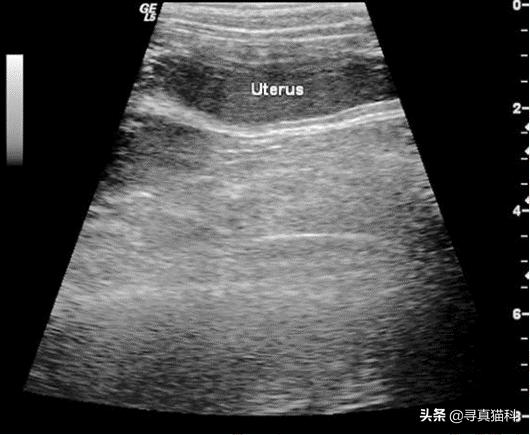

B超结果

(2)核心检查项目:B超、阴道分泌物抹片、血常规、生化,其中,B超的检查最为重要,常常需要靠B超来确诊。